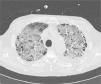

The guiding diagnosis was severe septicemia of respiratory origin, probably due to left basal pneumonia. Antibiotic treatment began with piperacillin/tazobactam and levofloxacin. The patient required admission to the intensive care unit for ventilatory and vasoactive support. Chest computed tomography (CT) showed signs of respiratory distress, but organizing pneumonia could not be ruled out (Fig. 1). Fiberoptic bronchoscopy did not reveal any macroscopic abnormalities, and no changes in cellularity were observed in bronchoalveolar lavage. Repeatedly negative cultures. H1N1 virus negative.